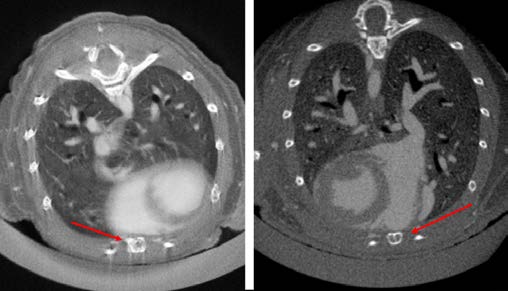

心拍や呼吸による動きは、CT画像のアーティファクトの原因となります。GX IIIは画像ベースの同期技術により、マウス、ラット、フェレットの心臓・肺イメージングを高精度に実現します。

撮影後、心臓や横隔膜に設定したROIをもとに独自アルゴリズムで同期処理を行い、アーティファクトを低減。心拍・呼吸周期の特定フェーズのデータを再構成することで、画質と定量精度を向上させます。

心臓・肺のin vivoイメージングなど、動きの影響を受けやすい研究に最適です。